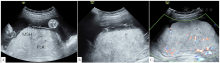

图2 病例3孕31<sup>+6</sup>周绒毛膜板下出血

注:A为胎盘前方近子面可见偏高回声,为绒毛膜板下出血,范围长径达11.5 cm,与正常胎盘组织有分界,有分层;B为中央型前置胎盘,绒毛膜板下出血位于胎盘脐带插入点附近;C为胎儿外生殖器呈"郁金香征";D为左侧子宫动脉可见切迹;E为出生后胎盘大体可见胎盘子面胎膜(羊膜+绒毛膜)与胎盘实质有分离,胎盘娩出过程中曾在其间积聚的不凝血已流失;F为出生后外生殖器证实为尿道下裂